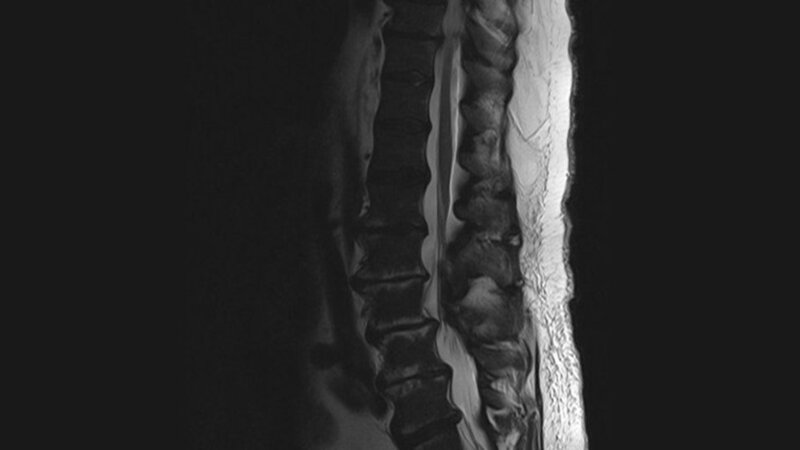

Schnittbilddiagnostik der Wirbelsäule (4.18)

In vorausgegangenen Publikationen wurden bereits Fallbeispiele von Zufallsbefunden aus dem Kreis hämatologischer Erkrankungen vorgestellt. Auch der aktuelle Beitrag kann diese Thematik mit dem Wirbelsäulenbefall durch eine Myelofibrose bei einer chronisch-myeloischen Leukämie (CML) fortsetzen.